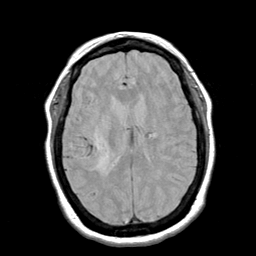

Cerebral hemorrhage, MR Study mr-pd -- Slice #14

[Home][Help][Clinical] Slice 14